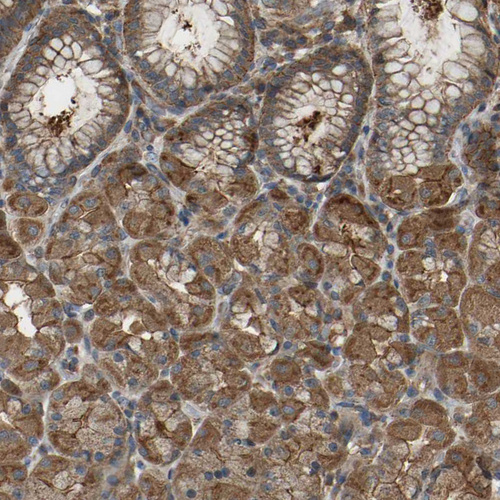

Immunohistochemical staining of human lymph node, placenta, stomach and testis using Anti-SAMD9L antibody HPA019465 (A) shows similar protein distribution across tissues to independent antibody HPA019461 (B).